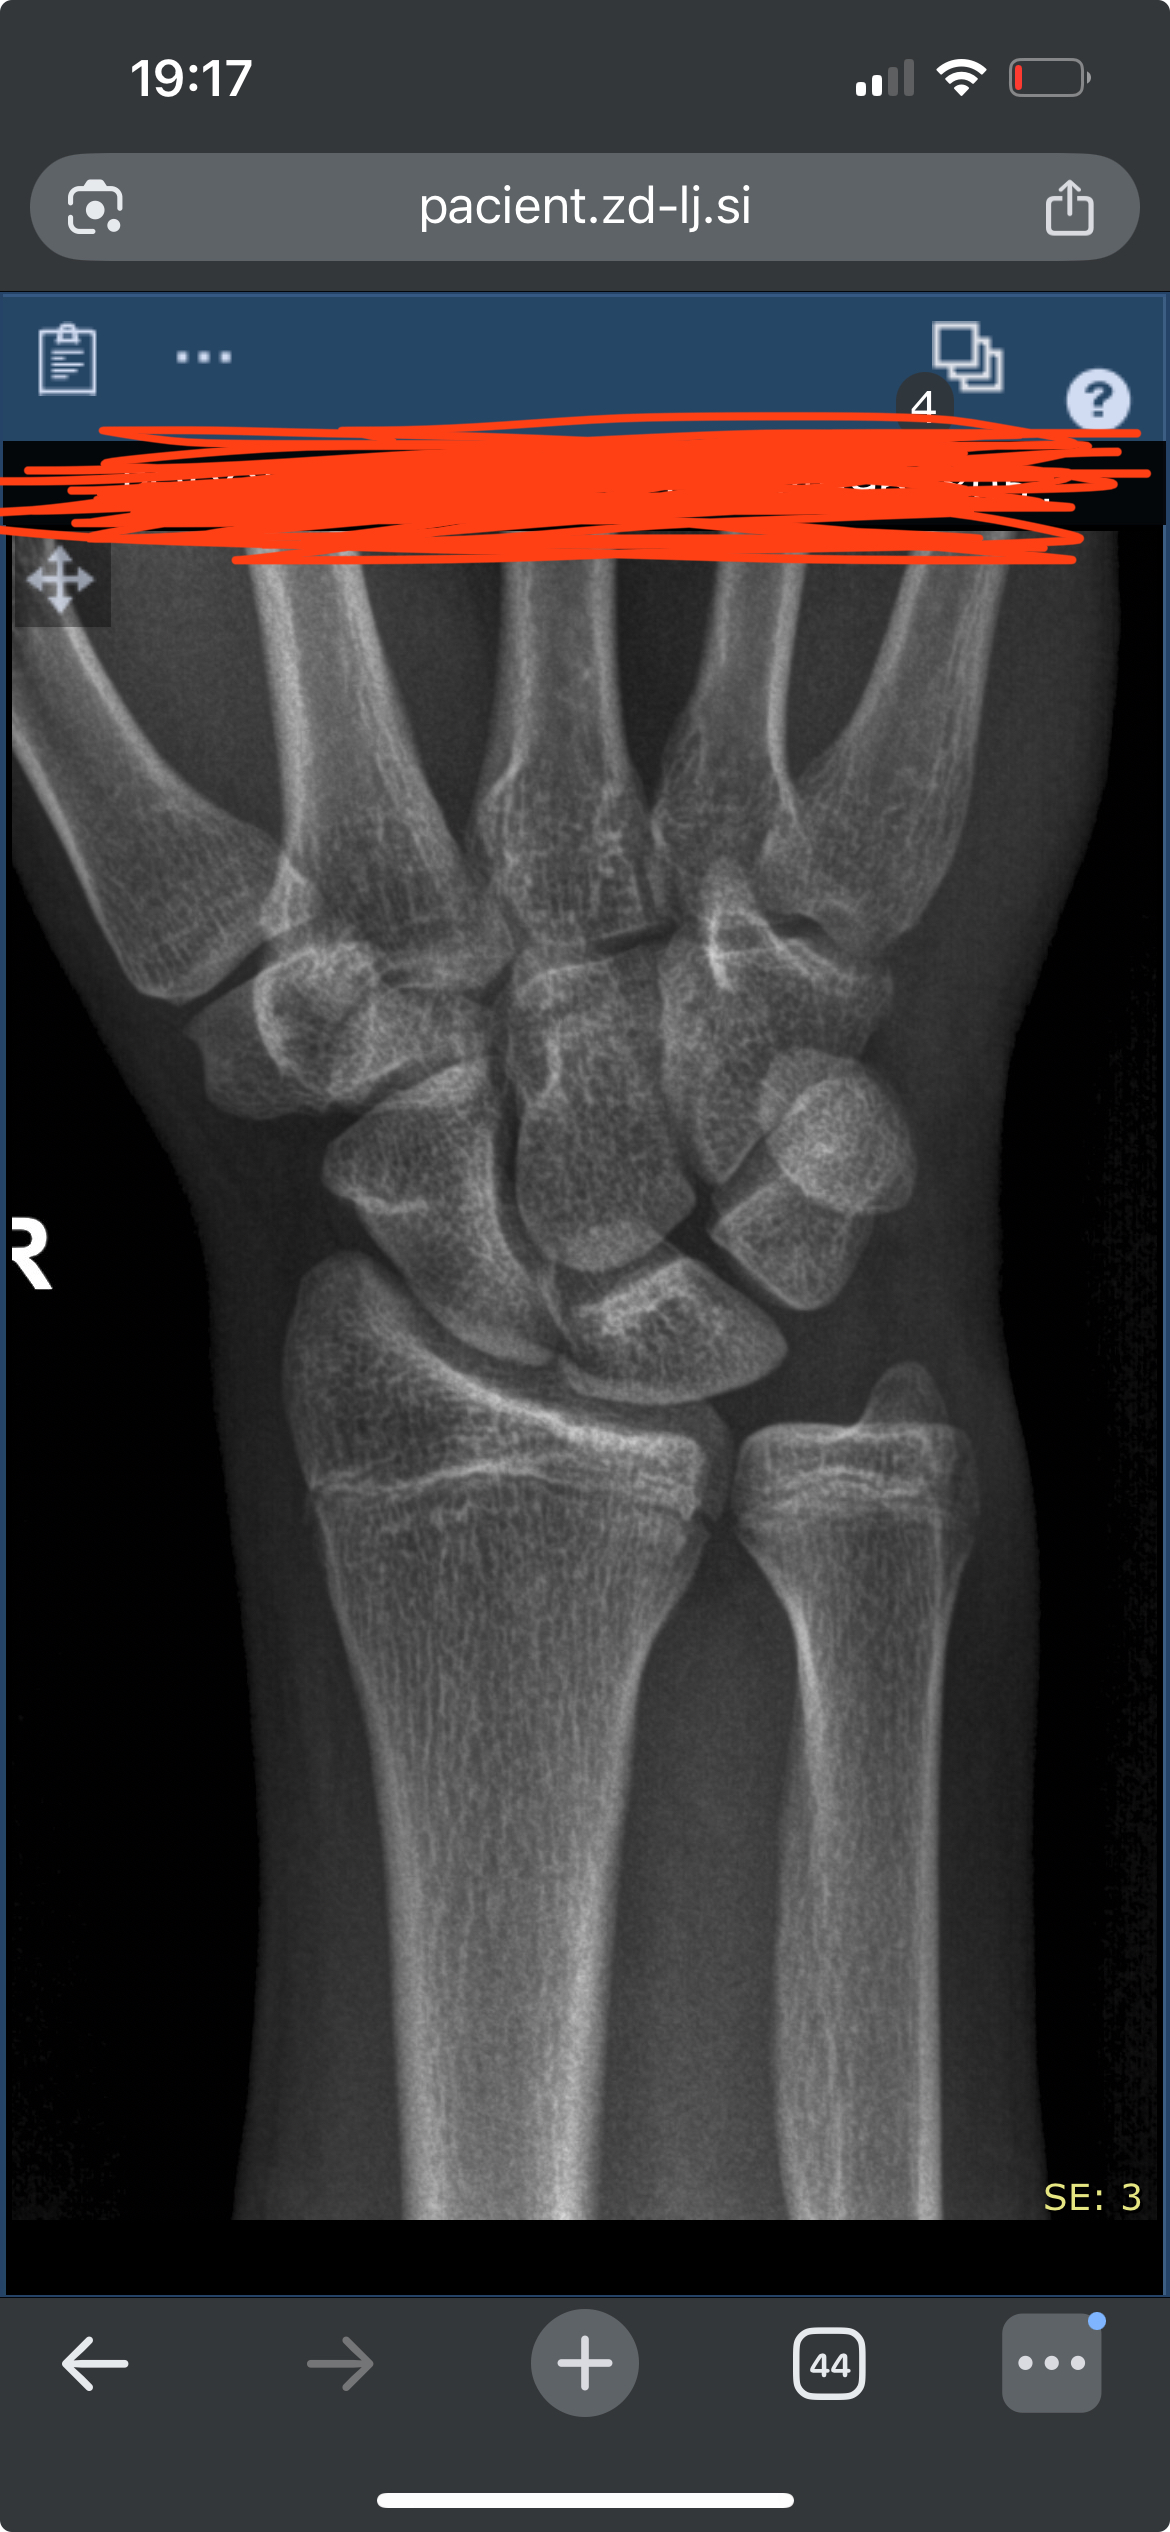

Havent posted here for a while. After talking with a private ortho he told my dentist to give me a referral to a maxilofacial surgeon.

Cannot wait for this, he said he thinks i have a high chance of having a bimax covered due to a misaligned and a deep bite.

IMG 0311